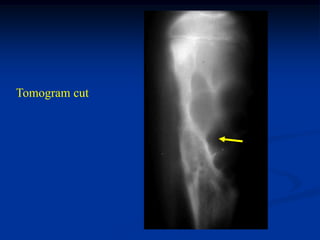

Case #637

12 year female with chondroblastoma prox femoral epiphysis

CT scan

Another CT cut